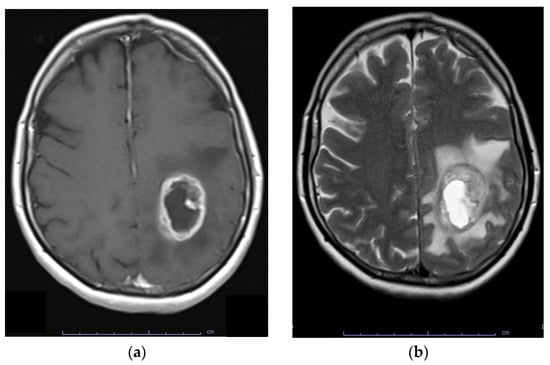

6. Diagnosis